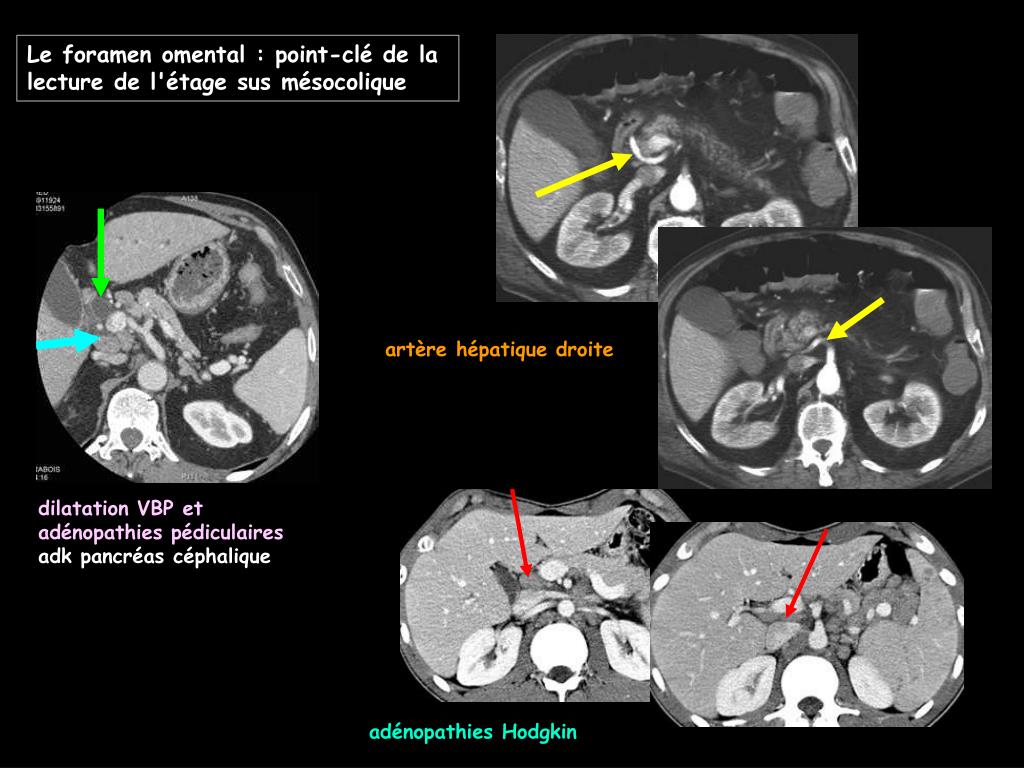

14. artère hépatique droite dilatation VBP et adénopathies pédiculaires adk pancréas céphalique adénopathies Hodgkin Le foramen omental : point-clé de la lecture de l'étage sus mésocolique